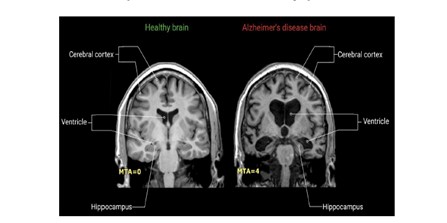

MRI images of Dementia cases in Figure 3, 4. AD leads to hippocampal atrophy and ventricular enlargement, healthy brain and brain images with AD are given in Figure 5 in an elderly, cognitively normal (CN) individual, an individual with amnestic mild cognitive impairment (aMCI) and an individual with Alzheimer's disease (AD) by obtaining images from the relevant literature.

Figure 4: AD leads to hippocampal atrophy and ventricular dilation. Healthy brain (left) and AD brain (right). AD leads to a decrease in hippocampal volume, shrinkage of the cerebral cortex, and ventricular dilation. MTA: medial temporal lobe atrophy; MTA = 0: no atrophy of the medial temporal lobe; MTA = 4: Severe volume loss in the hippocampus [60].